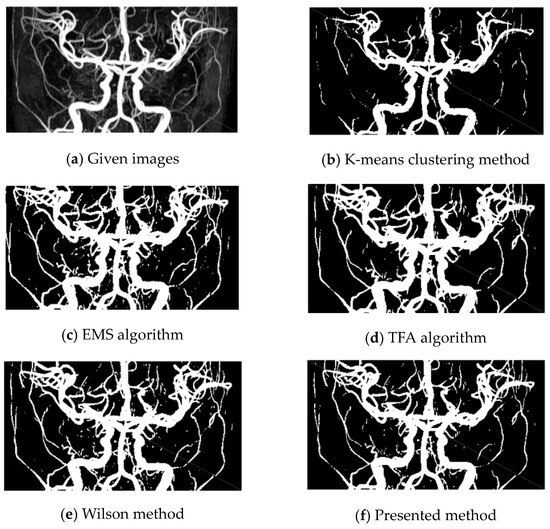

Example 2.

In this example, a 512 × 512 TOF-MRA Circle of Willis coronal image of the carotid vascular system is taken into consideration. Various methods, including K-means, EMS, TFA, Wilson, and the presented method, are used for vessel extraction.

The K-means clustering method (Figure 3b) fails to detect most of the vessels in the image. The EMS algorithm (Figure 3c) also produces unsatisfactory results. Both K-means and EMS methods do not provide acceptable vessel extraction.

The TFA algorithm (Figure 3d) is unable to detect some vessels, particularly the long ones, as evident when comparing the right parts of the given image (Figure 3a) with Figure 3d.

The Wilson method (Figure 3e) is also found to have poor results, creating artifacts in the left part of the image.

On the other hand, the presented method (Figure 3f) demonstrates acceptable results. It successfully extracts vessels while avoiding artifacts near the boundaries and maintaining the smoothness of the vessel boundary. Our method proves particularly effective in detecting thin vessels, essential for identifying pathological lesions and enhancing the delineation of vascular edges with low contrast.

Overall, the K-means, EMS, TFA, and Wilson methods exhibit limitations and unsatisfactory results in vessel extraction, whereas the presented method proves to be effective and successful in this regard.

Figure 3. Circle of Willis mip sagittal. (a) Given images; (be), results by K-means, EMS, TFA, and Wilson methods, respectively; (f) results by the presented method for Example 2.